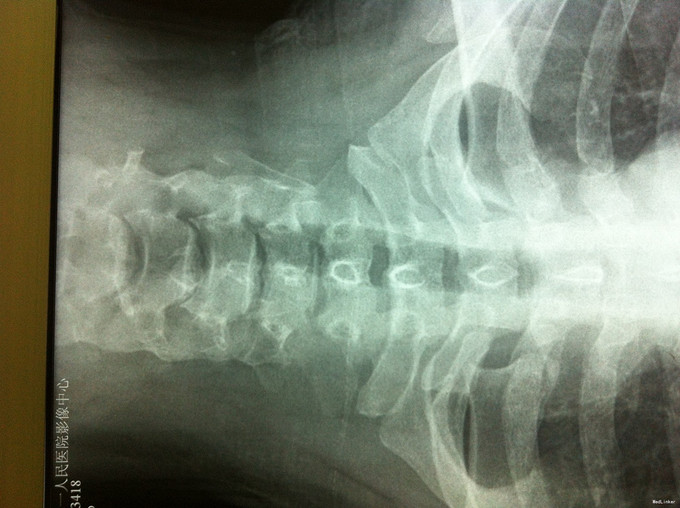

颈肩疼痛1年,加重伴左上肢疼痛、行走不稳1个月 患者1年前无明显诱因出现颈肩部疼痛不适,不伴四肢放射性疼痛、无力,劳累后加重,平卧休息可缓解。1个月前无明显诱因出现颈部疼痛加重,伴左上肢放射性疼痛,行走不稳、双足踩棉感,无高热、寒战,无低热、盗汗。

查体:左侧前臂及手感觉减退,右侧正常,左侧伸腕、伸肘肌肌力4级,右侧伸腕、伸肘肌肌肌力4-5级,双侧霍夫曼综合征阳性,双下肢肌张力高,膝腱反射+++,巴氏征阳性,辅助检查: X-ray:劲椎退行性变 CT及MR:颈椎间盘突出,腰5/6,6/7间盘突出并骨赘形成

诊断:脊髓型颈椎病 处理: 1、完善相关辅助检查,明确诊断,有无手术指证; 2、全麻下行颈椎前路减压,颈椎间盘突出并骨赘形成,行颈6椎体次全切,减压较充分。